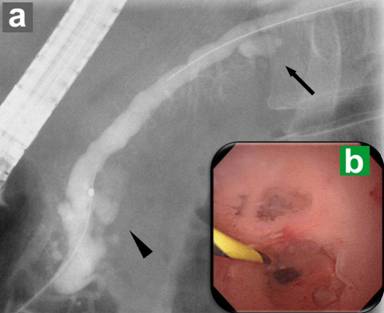

A 55-year-old Japanese male patient was admitted to our hospital for detailed examination of cystic lesions in the pancreas. He had neither a past history of diabetes mellitus nor a family history of malignancy, including PDAC. Physical examination showed no abnormalities. Laboratory examination revealed slight elevation of the serum carcinoembryonic antigen (CEA) level (4.3 ng/mL; reference range: 0-2.5 ng/mL at our institution), while the carbohydrate antigen (CA) 19-9 level (0.6 IU/mL) was within normal limits (reference range: 0-37 IU/mL). Enhanced CT and MRCP demonstrated multilocular cystic lesions in the pancreas head (25 mm in diameter) and body (16 mm in diameter) (Figure 1). Endoscopic ultrasonography (EUS) showed multiple branch duct IPMNs without findings suspicious for a mural nodule. Endoscopic retrograde pancreatography (ERP) showed a dilated duodenal papilla orifice caused by mucus hypersecretion and revealed that the cystic lesions in the pancreas head and body communicated with the main pancreatic duct; however, no irregularity of the main pancreatic duct itself was noted (Figure 2a). Subsequent peroral pancreatoscopy showed a fish egg-like appearance at the orifice of the dilated branch duct in the pancreas head, and pancreatic juice cytology revealed class V, highly suggestive of adenocarcinoma (Figure 2b).

Figure 2. Preoperative endoscopic retrograde pancreatography (ERP) and peroral pancreatoscopy. a. ERP shows cystic lesions in the pancreas head (arrowhead) and body (arrow), both of which communicate with the main pancreatic duct. The main pancreatic duct in the pancreas head is slightly dilated. b. Peroral pancreatoscopy reveals a fish egg-like appearance at the orifice of the dilated branch duct in the pancreas head. |